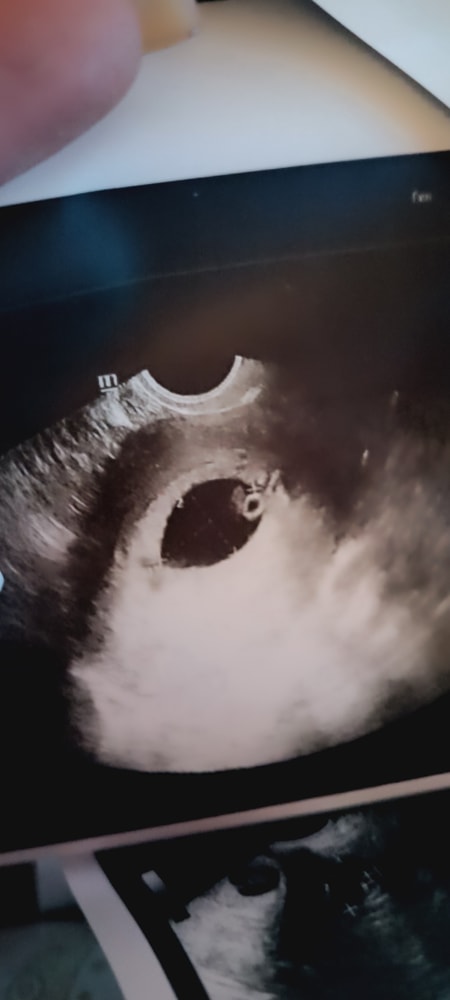

УЗИ в 7 недель и 5 дней

Маруся, и всё таки один)))) заново родилась сегодня))

Маруся, ничего не было, видимо реально ошибка была изначально. Показали плод, пуповину, желточный мешок. Как не крутила, один и всё) я 6 рад переспросила даже)) не знаю как смотрела прошлый узист, но неделю я была сама не своя.